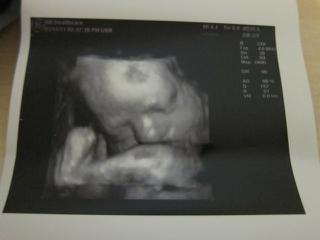

Ta prva foto je trochu rozmazana nozicka a foto pod nou dokaz kavoveho zrnka, 😉 na dvd je to lepsie vidiet, tam je to z roznych uhlov. 😉